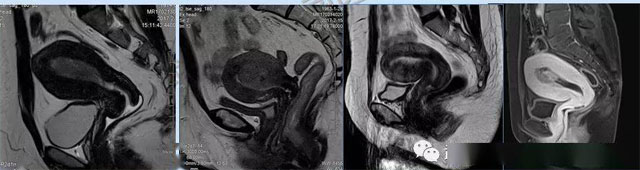

婦科疾病常常讓女性陷入了焦慮。主要是這類疾病婦女有難言之隱,癥狀隱匿,病情復(fù)雜。磁共振體檢車(chē)的金光火眼能力可以破解各種婦科難題。哪些情況需要使用磁共振檢查,檢查過(guò)程是否有不適。這些都是可以解決的。例如子宮常見(jiàn)疾病的磁共振診斷。

磁共振VS傳統(tǒng)檢查:有這些優(yōu)勢(shì)?無(wú)輻射安全系數(shù)高,磁共振沒(méi)有電離輻射,適合備孕跟孕婦檢查。它對(duì)軟組織有高清的成像效果,可以清晰的看到子宮各層的結(jié)構(gòu)??梢宰R(shí)別細(xì)小的肌瘤,早期的癌癥腫瘤。可以發(fā)現(xiàn)其他設(shè)備難以檢查到的深部子宮內(nèi)膜異位結(jié)節(jié)。多序列成像和增強(qiáng)掃描檢查,判斷腫瘤的良性準(zhǔn)確率高達(dá)90%以上。

磁共振檢查可以對(duì)子宮內(nèi)膜癌,精準(zhǔn)測(cè)量腫瘤侵犯子宮肌層的深度,發(fā)現(xiàn)微小轉(zhuǎn)移灶。復(fù)雜子宮肌瘤明確肌瘤位置、數(shù)量,區(qū)分良性肌瘤與惡性肉瘤,幫助制定微創(chuàng)手術(shù)方案。卵巢腫瘤鑒別數(shù)值分析、增強(qiáng)掃描,可識(shí)別畸胎瘤、巧克力囊腫、惡性腫瘤的特征。宮頸癌分期,判斷腫瘤大小、是否侵犯膀胱/直腸,指導(dǎo)選擇手術(shù)或放化療。生殖道畸形三維成像直觀顯示畸形類型,為矯正手術(shù)或輔助生殖提供依據(jù)。